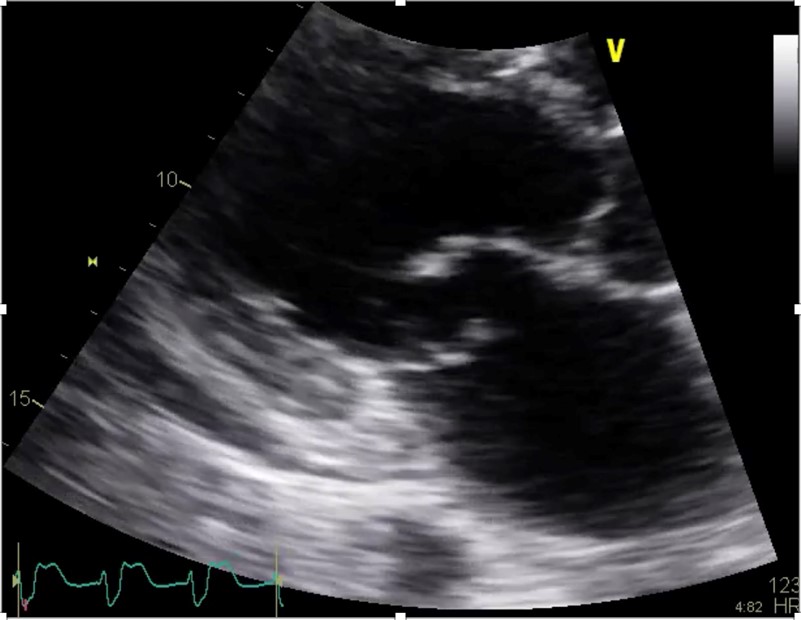

A point-of-care ultrasound was performed to help differentiate the cause of hypoxia and hypotension. The findings were consistent with the sequela of the patients recent RCA occlusion which demonstrated a newly identified flail posterior mitral valve leaflet and severe mitral regurgitation (Figures 1, 2, and 3). Subsequently, the patient was taken emergently to the cath lab for placement of an intra-aortic balloon pump (IABP). The balloon pump was adjusted to maximize the diastolic augmentation and minimize pre-systolic LV afterload to optimize the patient’s cardiac function.1 Once he was stabilized, the patient was taken to the operating room for a mitral valve replacement. After a prolonged hospital course, the patient survived to discharge and was sent to a skilled nursing facility for cardiac rehabilitation.

Figure 2. Close-up view of a flail posterior mitral valve leaflet and a small pericardial effusion in the parasternal long axis view